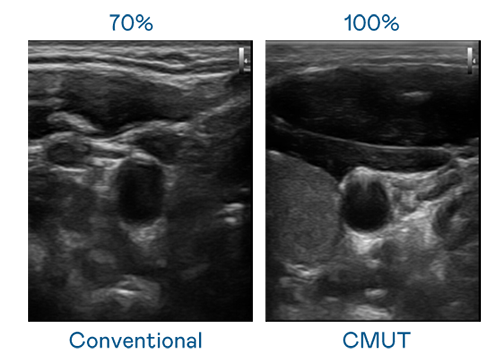

CMUT 技术是一种用电容式微机电元件来产生超音波讯号的技术。与传统 PZT 压电式技术相比,CMUT 频宽增加 30%,更宽频的超音波讯号让影像解析度大幅提升,是实现高影像品质医疗超音波扫描、促进精准医疗发展的关键技术。

大频宽带来超清晰影像

超音波影像的解析度高低,首先取决于探头能发出的讯号频宽。KU酷游 CMUT 可提供高清晰的超音波讯号,提供高频宽、高灵敏度、影像纹理细节更高的超音波影像,协助医护人员缩短影像判读时间及利用精准的医疗影像进行诊断。